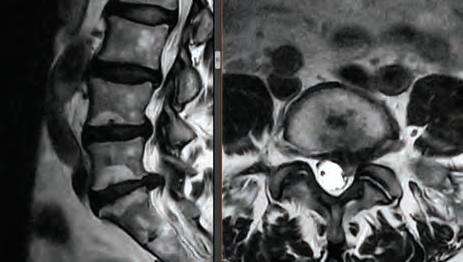

For board-certifid, fellowship trained orthopedic spine surgeon

Dr. Stephen P. Courtney, patients come fist. It’s an ethos that developed early on in his life and one that has helped guide him in his journey to earn a distinguished reputation among his professional colleagues, medical peers and, most importantly, his patients.

Led by Dr. Courtney, the skilled team at Advanced Spine Center cares for patients with neck and back pain using a wide array of the most state-of-the-art tools and techniques—from conservative physical therapy and injection therapy—to advanced pain manage-

ment, as well as surgical intervention. We employ the latest in minimally invasive spine surgeries, in addition to cutting-edge replacement technology. Incorporating both high tech and high touch, we get our valued patients back to their lives so they can enjoy all the activities they love.

SURGERY: L5/S1 360° LUMBAR FUSION

SURGERY: LEFT L5/S1 MICRODISCECTOMY

SURGERY: C4/C5, C5/C6, C6/C7 ACF (ANTERIOR CERVICAL FUSION)

SURGERY: L4/5, L5/S1 360° LUMBAR FUSION

Dr. Courtney is a board-certified orthopedic spine surgeon located in Plano, Texas. A Louisiana native, he attended Louisiana State University for medical school, and completed residency at Texas A&M followed by a fellowship at the Florida Neck and Back Institute.

SPECIALTIES:

• Back Pain

• Neck Pain

• Spine Pain

• Disc Replacement

• Microdiscectomy

• Spinal Fusion

• Minimally Invasive Surgery

• Steroid Injections

• Physical Therapy